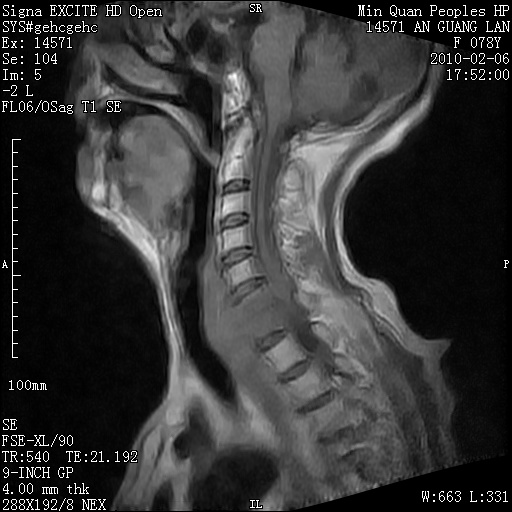

标题: MRI2763:C6、C7椎体病变性质?

f,78y,颈部与双上肢阵发性剧痛40余天。ct可见c6、c7椎体虫蚀样破坏,其间椎间隙变窄(没有图片资料可供上传)。

考虑椎体结核并椎旁脓肿。

支持 c6、7椎体结核并椎旁冷脓肿形成。

考虑:c6/7椎体结核并椎旁脓肿形成,建议增强扫描。

单从影像表现此诊断不难,还应该结合临床资料排除其他